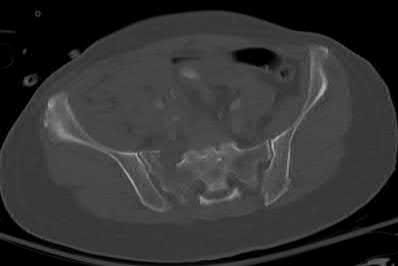

A 35 year-old female presents after prolonged extrication from a motor vehicle collision complaining of severe pelvic pain. Physical examination reveals diminished perianal sensation. She is otherwise neurologically intact. Figures A through D are radiographs and representative CT cuts of her injury. Which of the following nerve roots has likely been injured by the acute trauma?

The clinical scenario is consistent with a high-energy sacral fracture. The radiographs in figures A and B demonstrate a sacral fracture with posterior displacement of the right hemipelvis seen on the inlet view. Figures C and D are axial and sagittal CT images which show a displaced fracture of the right

hemisacrum along with a transvere fracture component through the S3 body . Diminished perianal sensation is concerning for an S2 nerve root injury.

Mehta et al reviewed the current management of sacral fractures. They note that the S1 and S2 nerve roots are more likely to be injured with sacral fractures as they occupy 1/3 to 1/4 of the neural foramina, as opposed to S3 and S4, which only occupy 1/6 of the neural foramina.

Robles reviewed the current literature to ascertain principles of evaluation and treatment for transverse sacral fractures. The author notes that injury to nerve roots S2 to S5 is manifested by impairment of urinary and anal continence and sexual function.